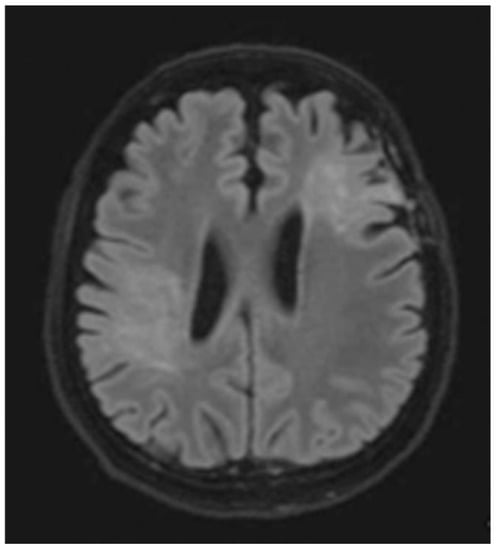

Figure 5.

Axial T2W images of the same patient showing extensive hypersignal–intensity lesions scattered at juxtacortical region, subcortical region, deep white matter and periventricular white matter of bilateral cerebral hemispheres.